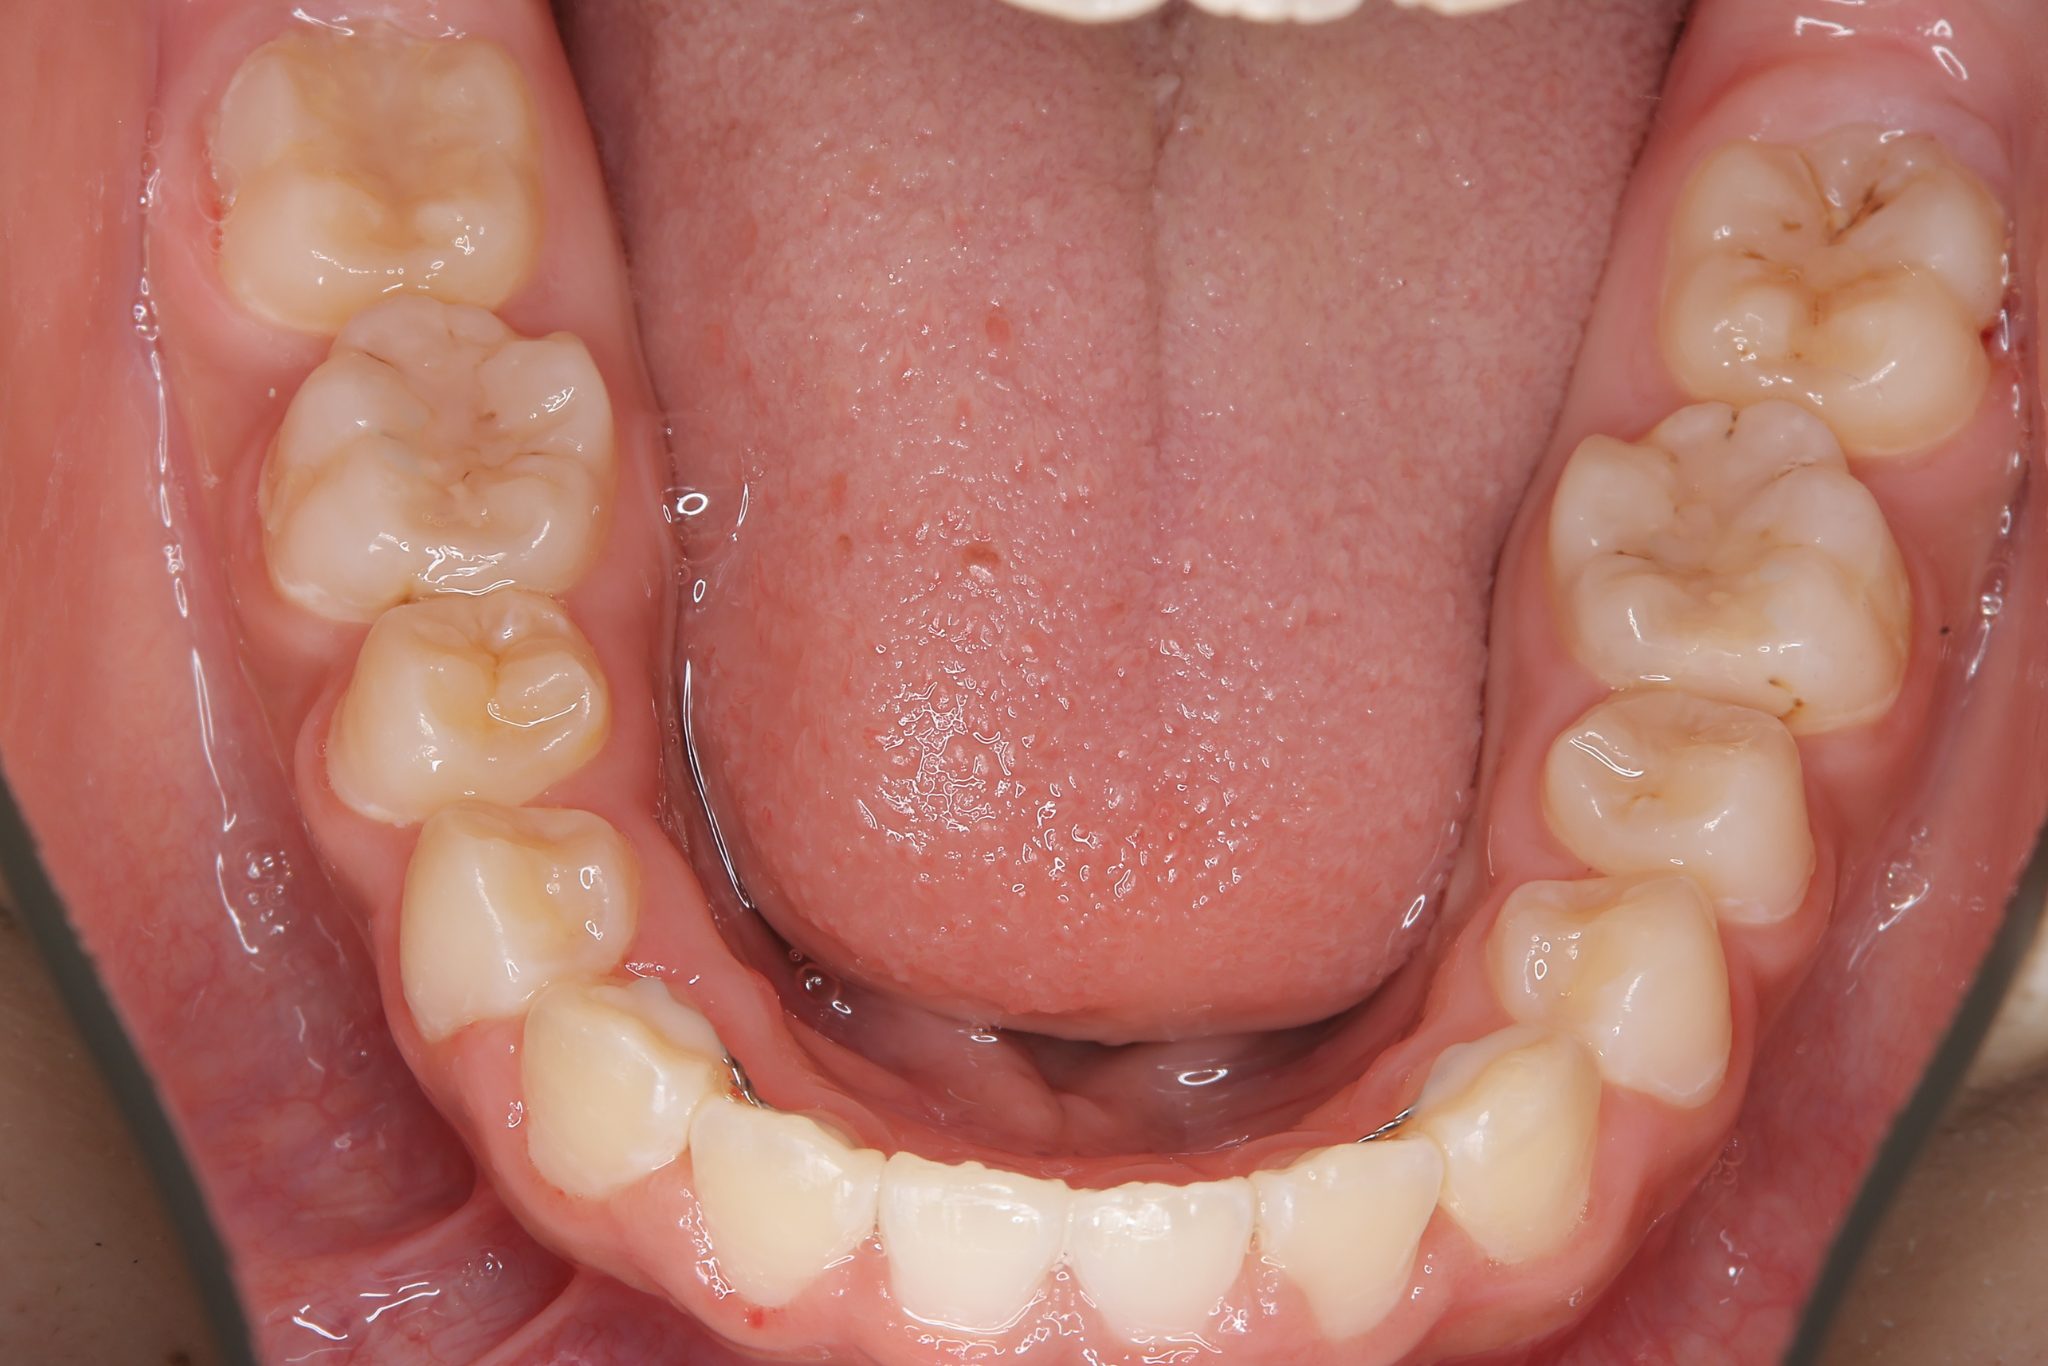

ビフォー

全顎ワイヤー矯正 症例_474

主訴 歯並びがガタガタで前歯が出ている

施術内容 小児矯正1期治療

治癒期間 1年5か月間

費用 1,020,800円(税込)